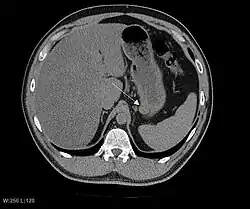

Радиологические исследования

Радиологические исследования используются для уточнения локализации новообразования, выявления признаков инвазии и метастазирования. Проявления ГИСО варьируют в зависимости от размера опухоли и поражённого органа. Диаметр опухоли может составлять от нескольких миллиметров до более 30 см. Крупные опухоли обычно вызывают клинические проявления, бессимптомные опухоли обычно небольших размеров и имеют лучший прогноз.[3][16] Большие опухоли чаще ведут себя более злокачественно, однако и небольшие ГИСО могут иметь агрессивное течение.[17]

Небольшие ГИСО

Так как ГИСО происходят из мышечного слоя (который располагается глубже слизистого и подслизистого слоёв), небольшие ГИСО чаще визуализируются как подслизистое или внутристеночное объёмное образование. При исследовании желудочно-кишечного тракта с барием обычно выявляются ровные контуры образования, формирующие прямой или тупой угол со стенкой, что наблюдается и при любых других интрамуральных процессах. Поверхность слизистой интактна, за исключением случаев изъязвления, которые присутствуют при 50 % ГИСО. При КТ с контрастным усилением, небольшие ГИСО обычно визуализируются как интрамуральные образования с ровными, чёткими контурами и гомогенным контрастированием.

Крупные ГИСО

По мере роста опухоли, она может проецироваться снаружи от органа (экзофитный рост) и/или в просвете органа (интралюминальный рост); чаще всего ГИСО растут экзофитно, таким образом большая часть опухоли располагается в проекции брюшной полости. Если увеличение объёма опухоли опережает рост её кровоснабжения, опухоль может некротизироваться в толще, с формированием центральной зоны жидкостной плотности и кавитацией, что может приводить к изъязвлению и формированию соустья с полостью органа. В этом случае исследование с бариевой взвесью может демонстрировать газ, уровни газ/жидкость или депонирование контрастного препарата в этих областях.[17][18] При КТ с контрастным усилением крупные ГИСО выглядят негомогенно, в связи с неоднородностью структуры опухоли, обусловленной участками некроза, кровоизлияниями и полостями, что радиологически проявляется контрастированием опухоли преимущественно по периферии.[16]

Злокачественность может проявляться локальной инвазией и метастазами, обычно в печень, сальник и брюшину. Однако встречаются случаи метастазирования в кости, плевру, лёгкие и забрюшинное пространство. По сравнению с аденокарциномой желудка или лимфомой желудка/тонкой кишки, злокачественная лимфаденопатия при ГИСО не типична (<10 %).[16] При отсутствии метастазов радиологическими признаками злокачественности являются большие размеры опухоли (>5 cm), гетерогенное контрастирование после введения контрастного препарата и наличие изъязвлений.[3][16][22] Также явно злокачественное поведение (без учёта опухолей со злокачественным потенциалом) реже наблюдается при ГИСО желудка, с отношением доброкачественных опухолей к явно злокачественным 3-5:1.[3] Даже в случае наличия радиологических признаков злокачественности, следует учитывать, что они могут быть обусловлены другой опухолью; окончательный диагноз должен быть установлен иммуногистохимическим методом.

Методами выбора в диагностике ГИСО являются КТ и МРТ,[23]:20–21 и, в некоторых случаях, эндоскопическое УЗИ. Томографические методы позволяют уточнить органную принадлежность опухоли (что может быть затруднительно при её больших размерах), визуализировать инвазию в соседние органы, асцит и метастазы.